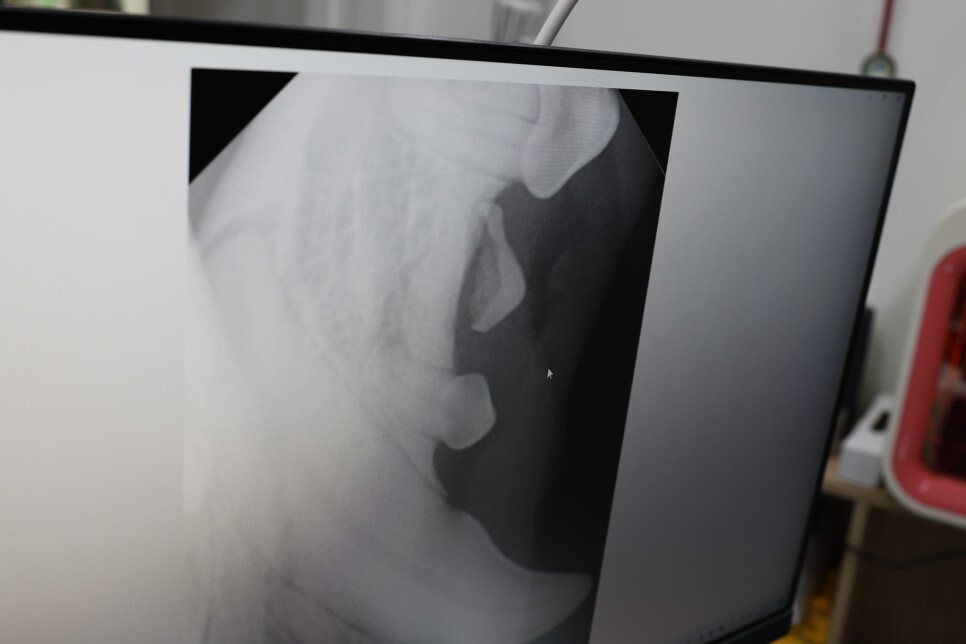

이제 치과 엑스레이를 찍을 시간.

아무 이상 없기를 바라는데

원장님은 육안으로 아이 치아 상태를 보더니

치석이 나이에 비해 아주 많아서

치아 질환이 있을 수도 있다고 하는데

자세한 것은 찍어봐야 ..

부위별로 촬영하는 하원

삐뽀 삐뽀!!!

이상 소견 발견

치아 하나가.. 이상함..

이것은 치석 제거 후 발치하기로.